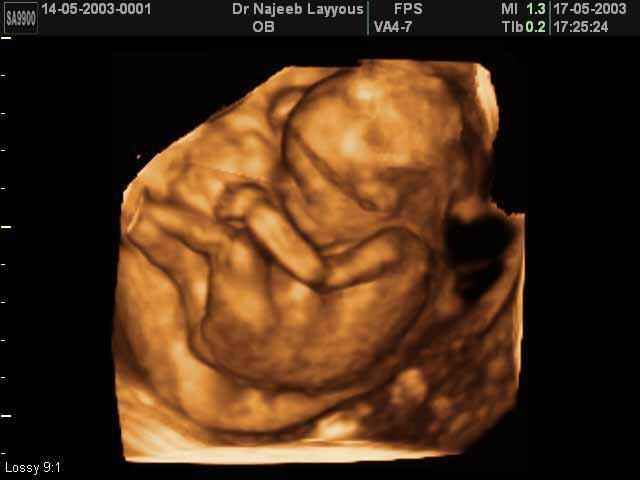

- Fetal Behavior Ultrasound Photos